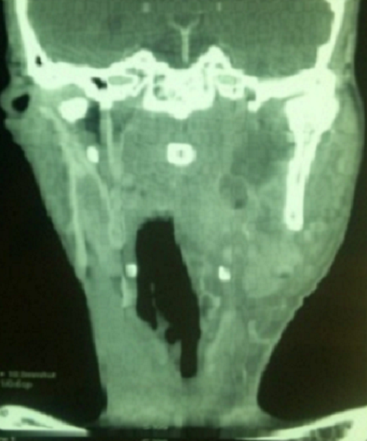

Les abcès para-pharyngés surviennent surtout chez les immunodeprimés notamment les diabétiques. Ce sont des infections préstyliennes dont l'origine est le plus souvent dentaire. La TDM est systématique et urgente vu l'intérêt diagnostique, topographique et thérapeutique. Patient âgé de 52 ans diabétique de type II a consulté pour une odynophagie et un torticolis évoluant depuis 3 jours. L'examen physique a objectivé une fièvre à 39°C, des caries dentaires, une tuméfaction cervicale gauche de 4 cm de grand axe, douloureuse avec des signes inflammatoires en regard et des adénopathies centimétriques cervicales et sous maxillaires. L'examen oropharyngé a révélé une tuméfaction de la paroi latéro-pharyngée déjetant l'amygdale en dedans. A la biologie, il avait un syndrome inflammatoire. Son diabète était déséquilibré. Les prélèvements bactériologiques étaient négatifs. La TDM cervicale a objectivé une collection para pharyngée gauche. La TDM thoracique n'a pas trouvé de médiastinite. Le traitement s'est basé sur une antibiothérapie intraveineuse de 15 jours faite d'amoxicilline-acide clavulanique, métronidazole et gentamycine associée à un drainage chirurgical. Une équilibration du diabète était réalisée en parallèle. Des soins dentaires ont été indiqués en vue de prévenir d'autres complications infectieuses sur ce terrain diabétique. L'évolution était favorable sur le plan clinique et biologique.